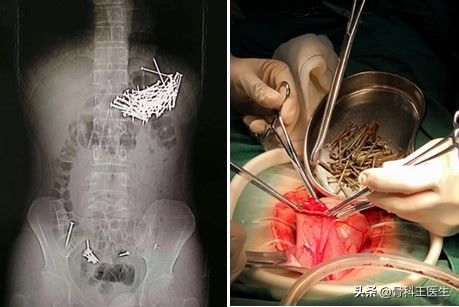

下面再看一个肚子取异物的故事,这个不是我院取的:

有的异食癖患者什么都吃,管他钉子不钉子,最后只能手术取出了!珍爱生命,少吃零食!